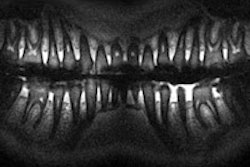

SWIFT, a novel MRI technique, can simultaneously image both hard and soft dental tissue. Image courtesy of Djaudat Idiyatullin, Curt Corum, and Steen Moeller (CMRR).

"The biggest advantage for dentistry is that SWIFT can simultaneously see hard and soft tissue," Dr. Nixdorf said. "You can see inside the tooth, the tooth pulp, and you don't have to look for bone loss because you can see the water content right away."

Idiyatullin will provide an overview of SWIFT and its potential applications in clinical dentistry, describing in vivo SWIFT experiments performed at the University of Minnesota. In these experiments, the researchers found that SWIFT MRI offered simultaneous visualization of densely mineralized tissues (enamel and dentin) and soft tissues in the pulp, within clinically relevant scanning times (less than 10 minutes) and without the use of ionizing radiation.